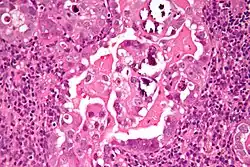

Micrograph of uterine serous carcinoma demonstrating characteristic psammoma bodies and cilia. H&E stain.

Characteristic discohesiveness of cells (like falling apart) around fibrovascular cores

Histopathologically, uterine serous carcinomas is typically characterized by (1) nipple-shaped structures (papillae) with fibrovascular cores (2) marked nuclear atypia (irregularities in the nuclear membrane, enlarged nuclear size), (3) psammoma bodies and (4) cilia. These are general findings in serous tumors which are also seen in such tumors in other anatomic locations.